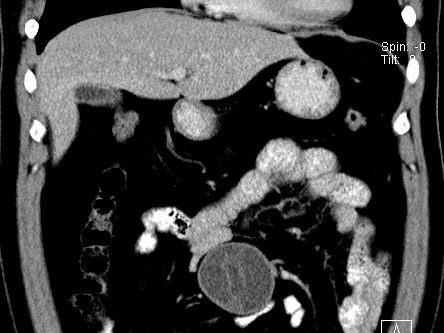

(腹腔)神经鞘瘤

男,48岁,间断性下腹不适1年。

手术探查

:距回盲部28厘米处肠系膜根部可见5*7cm左右包块,质中等硬度,活动度尚可,肝、胆、胰、脾肾未见明显异常。

病理

:(腹腔)

神经鞘瘤

,伴出血、坏死及囊性变,伴淋巴结反应性增生。

免疫组化结果

:sma(-), desmin(-), cd117(-), s-100(+++), nf(-),vimentin(+++).